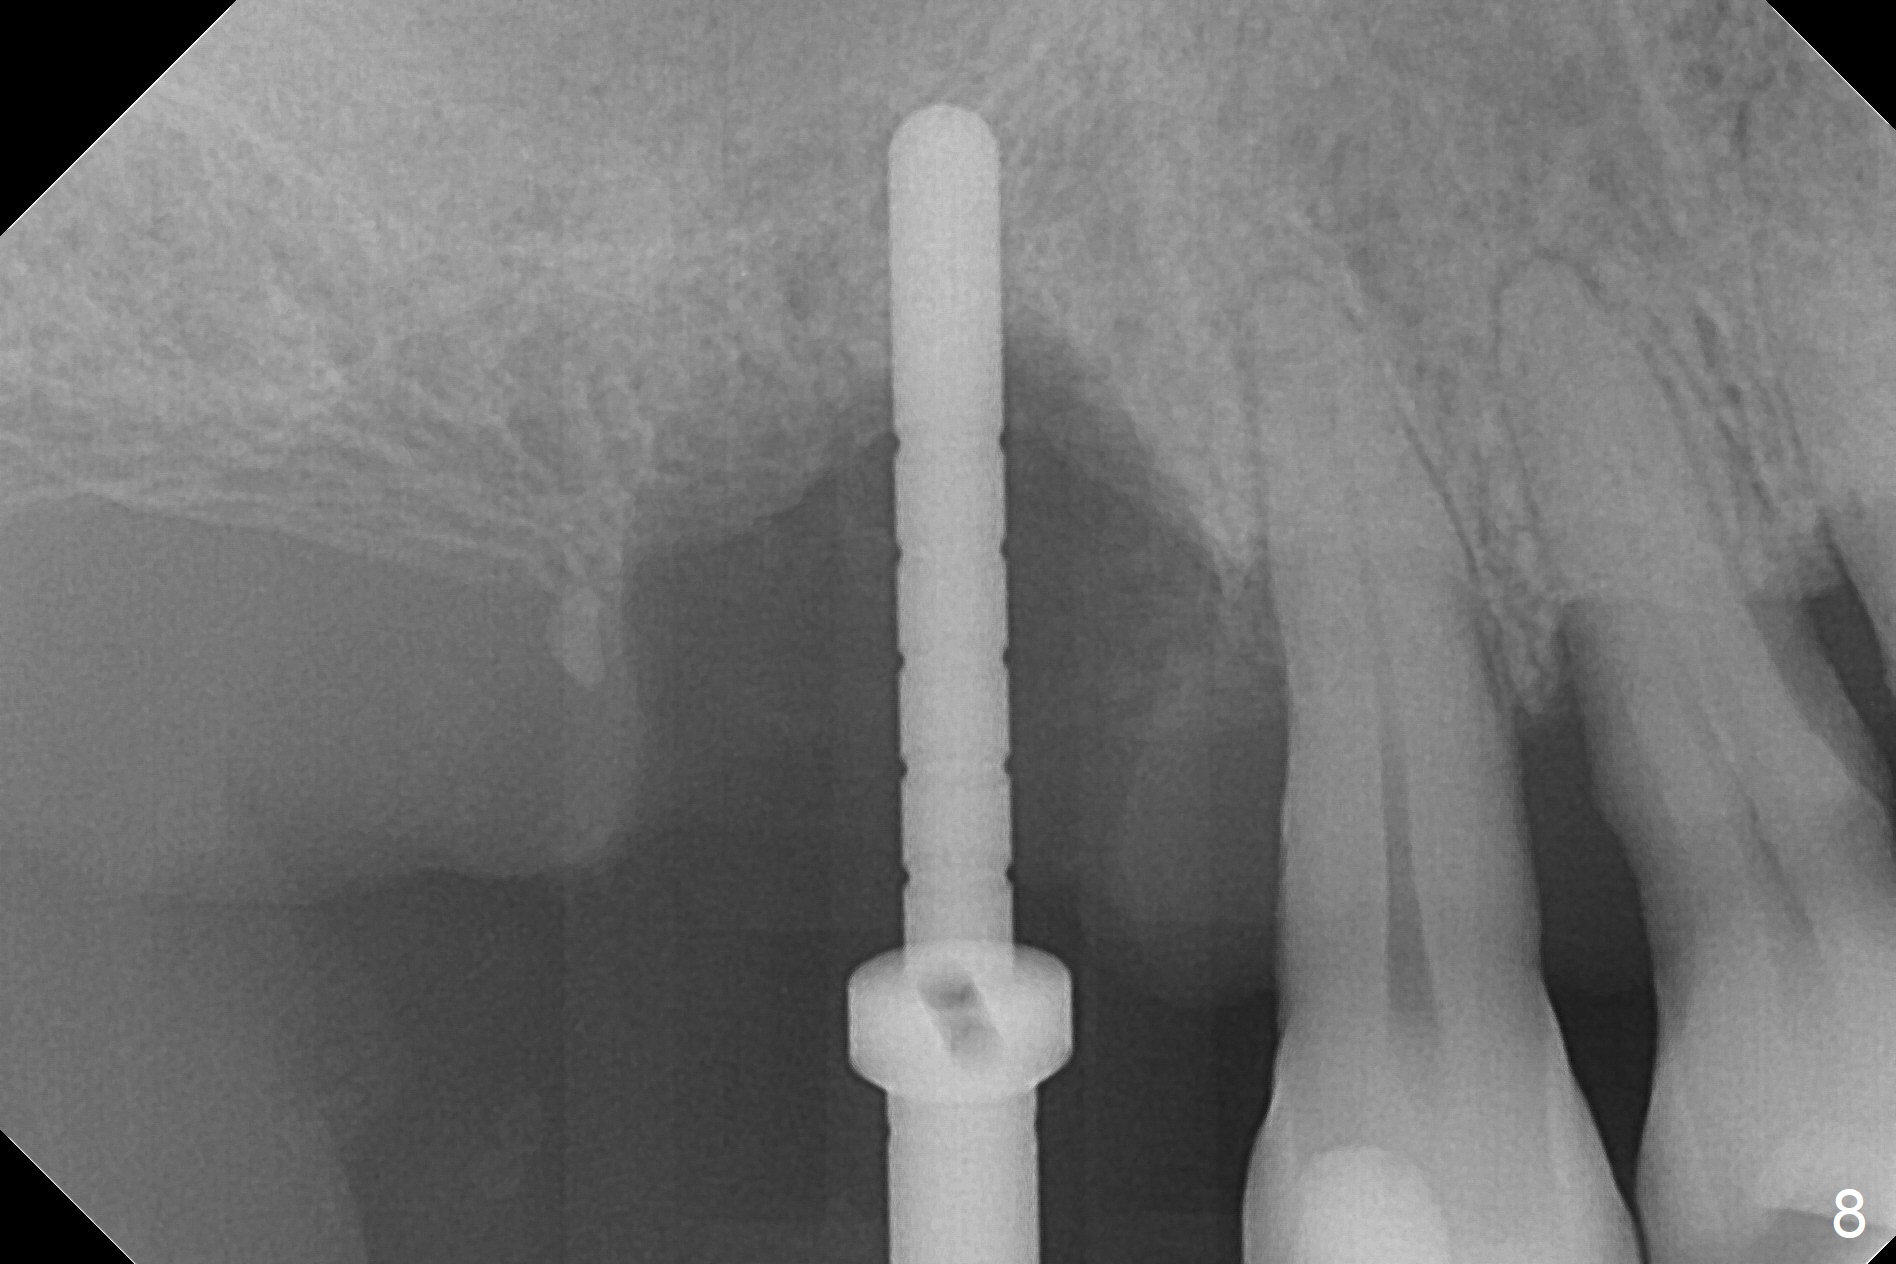

Buccal Socket Placement

After extraction of the tooth #3 (Fig.1,2), the palatal socket (P) is as wide as the buccal one (B; Fig.3,4 (socket impression)), as compared to the roots), suggesting bone loss is more severe palatally than buccally. There is a circular area in the buccal slope of the palatal socket, in which the bone looks thin (purplish: presumably the sinus membrane underneath, Fig.5,7 (blue circle)). It appears that the palatal slope of the buccal socket (Fig.6, 7 red dashed line) is the most appropriate site for osteotomy (Fig.8). Prior to inserting 5.3 mm tap drill (Fig.9), the mesiopalatal region of the osteotomy (corresponding to the blue circle in Fig.7) perforates without sinus membrane tear. A small piece of Osteogen plug is placed in the perforation before inserting a 5.3x10 mm SM implant (Fig.10,11). Following placement of another piece of Osteogen plug in the palatal socket and of a 4.8x7(6) mm abutment, mineralized cortical and cancellous bone is placed (*). Collagen plug and an immediate provisional are used to close the socket opening. CT taken 11 months post cementation shows that the implant is placed within bony boundary, although buccally (Fig.12 B). Bone graft seems to heal in the sinus (Fig.13 (sagittal section),14 (coronal section) white * (Osteogen plug) and in the socket (brown * (allograft and Osteogen)).